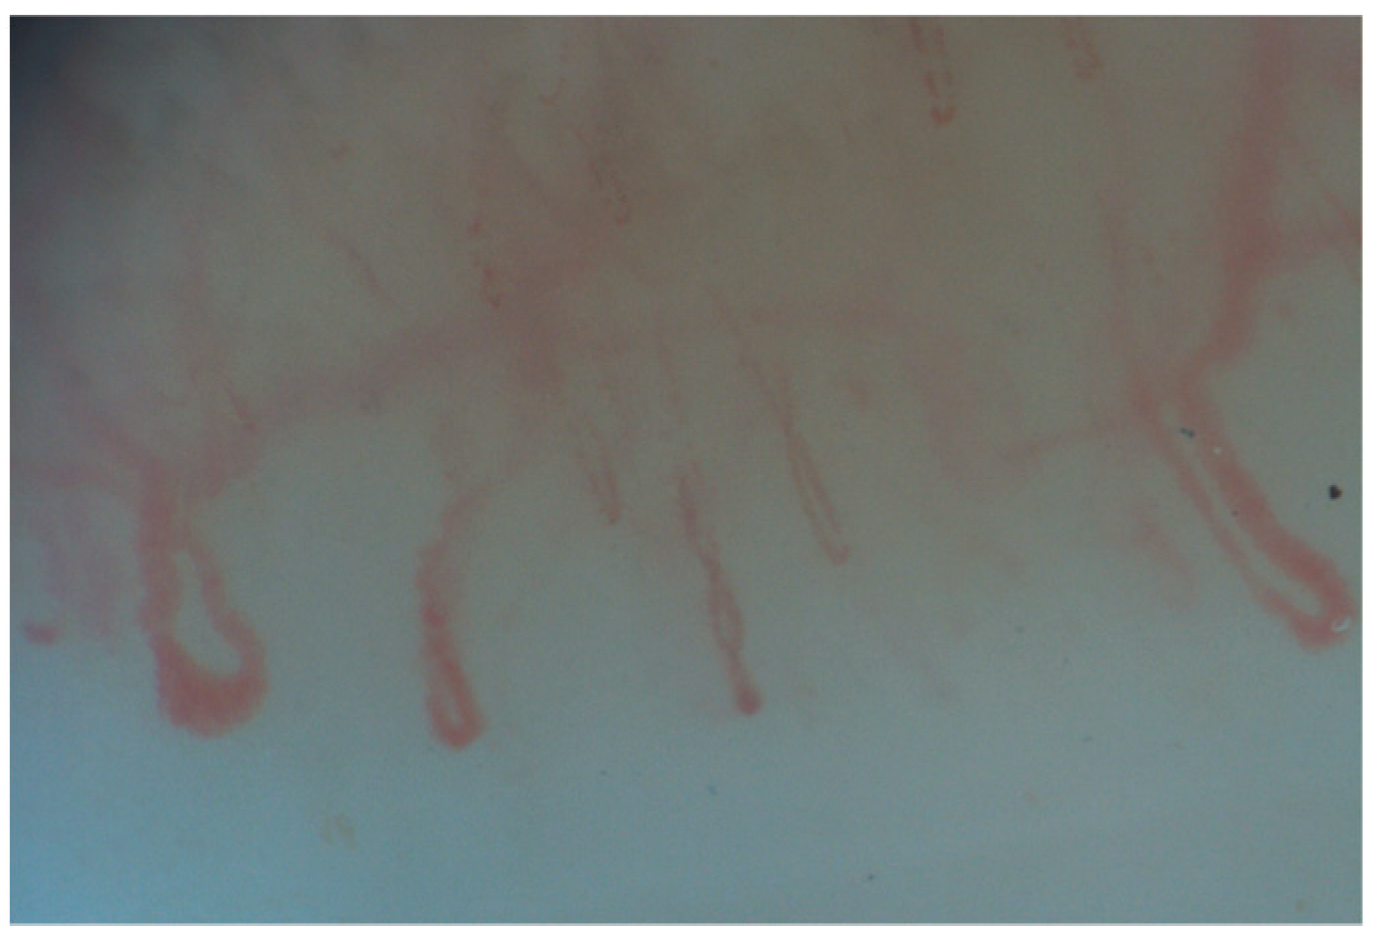

2. Normal Capillary Pattern